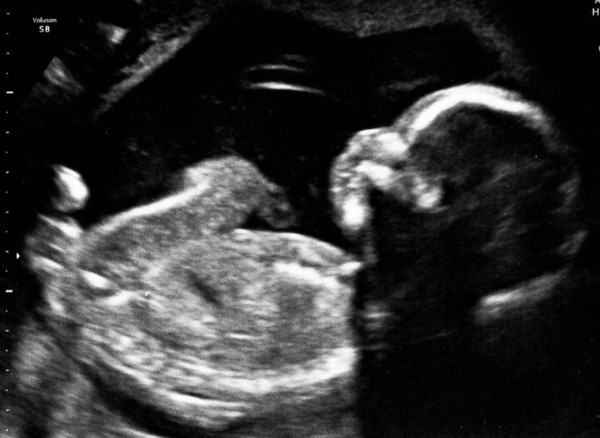

Got a second attempt at my 20 week scan on Oct 15th at 9am

hopefully baby will co operate this time.

I was at the hospital yesterday for an appointment to see dietician, midwife and doctors. Docs confirmed that after 2 previous c sections I will be having another around 39 weeks and they also looked through my scan report and said I'll need another scan at 32 weeks because my placenta is anterior and low.